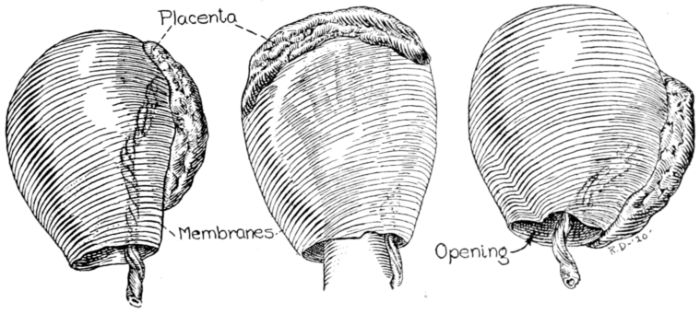

| 22. | Photograph of placental vessels | 72 |

| 23. | Maternal surface of the placenta | 74 |

| 24. | Fetal surface of the placenta | 75 |